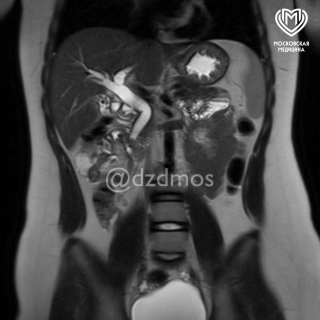

Врачи провели исследование и на МРТ увидели много камней диаметром до 3 мм, а один камень перекрывал холедох — общий желчный проток, это угрожало жизни девочки.